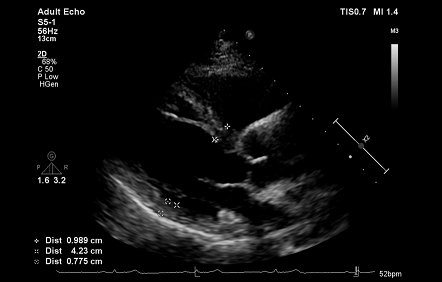

术后超声心动图